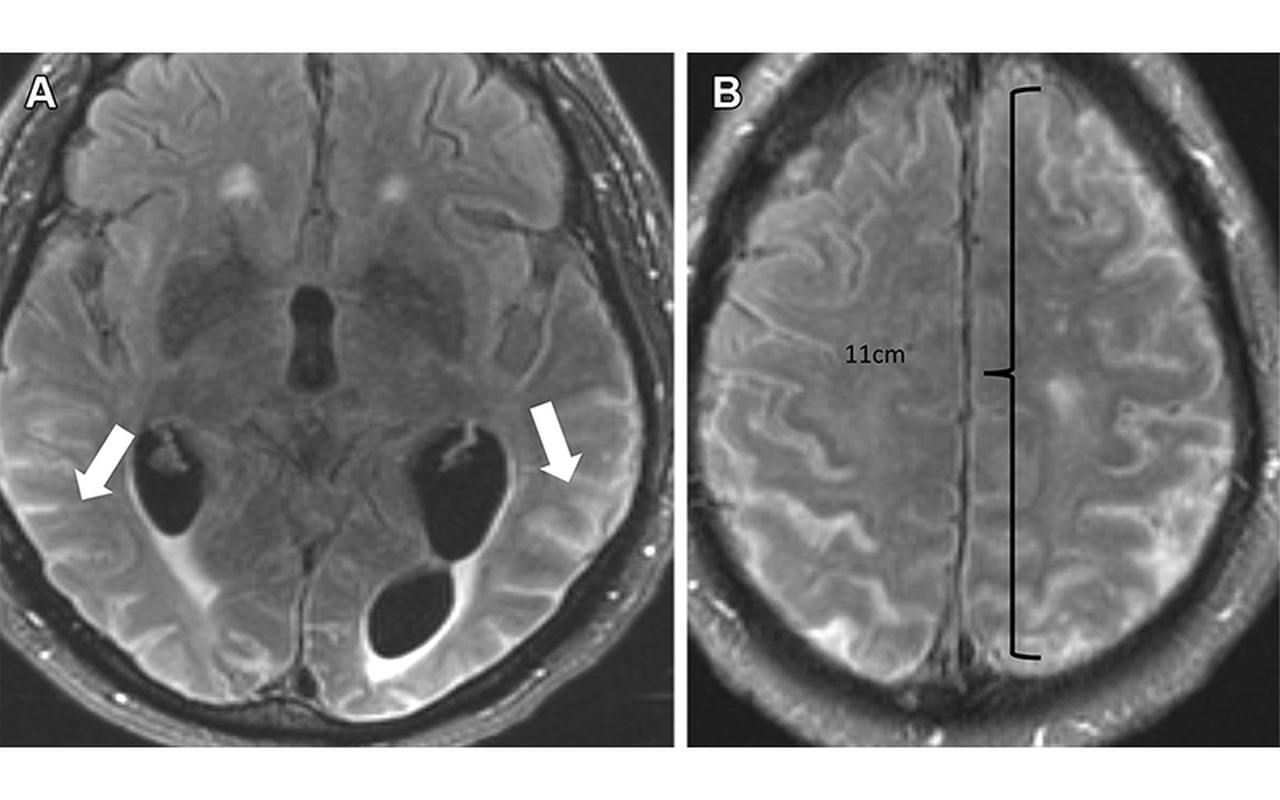

The abnormalities have been further classified into two categories, ARIA-E, representing edema and/or effusion, and ARIA-H, representing hemorrhage. ARIA is thought to be caused by increased vascular permeability following an inflammatory response, leading to the leakage of blood products and fluid into surrounding tissues.

Patients with ARIA sometimes have headaches, but they are usually asymptomatic and only diagnosable with MRI.

ARIA-E is the most common side effect of monoclonal antibody treatment.

In two phase III trials, 35% of patients on the approved dose had ARIA-E. These trials also showed that most ARIA-E cases were clinically asymptomatic and that 98% were resolved at follow-up imaging. ARIA-E occurred most frequently between three and six months of treatment, with incidence sharply dropping after the first nine months.

ARIA-H typically occurs in about 15 to 20% of patients treated with monoclonal antibodies. Unlike ARIA-E, ARIA-H is not transient and does not resolve over time.

The vast majority of patients with ARIA-E can continue therapy either with or without temporary suspension. However, in ARIA-H patients, therapy decisions depend on the severity of ARIA-H and whether it is stabilized. The detection of 10 or more new microhemorrhages requires permanent discontinuation of therapy.